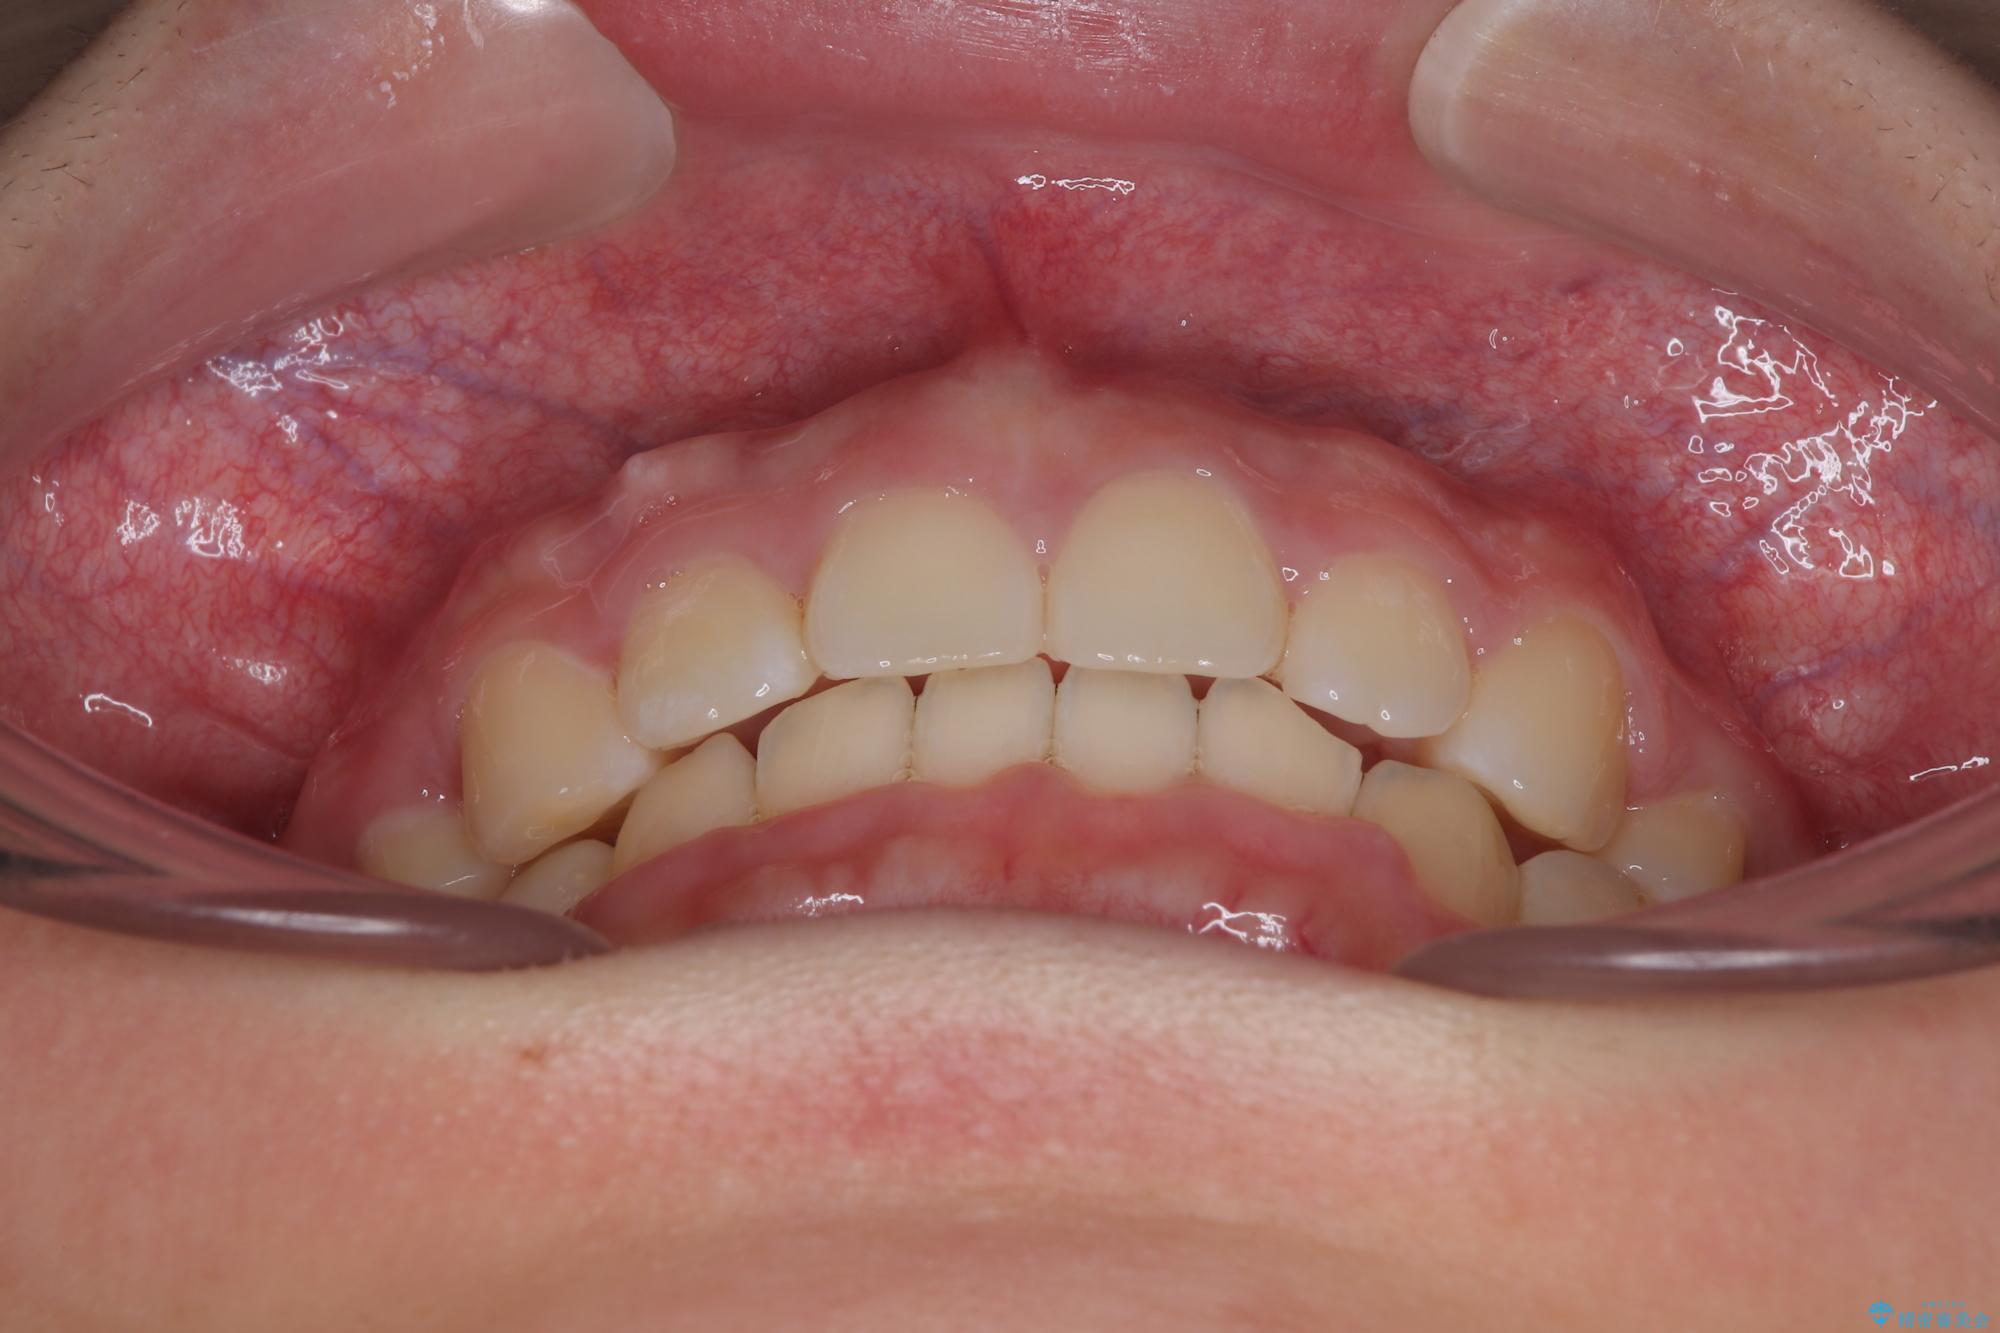

- 上顎前歯が飛び出していて唇がうまく閉じられないとのことで来院された患者様です。

くちばしのように前歯が突出していたため、口元を積極的に引っ込めるために、上下左右の小臼歯4本を抜歯することとしました。

また、上顎歯列が下顎に対して前方位に位置していたため、補助装置を用いて上顎歯列を後方に移動させ、より積極的に口元を下げるようにしました。